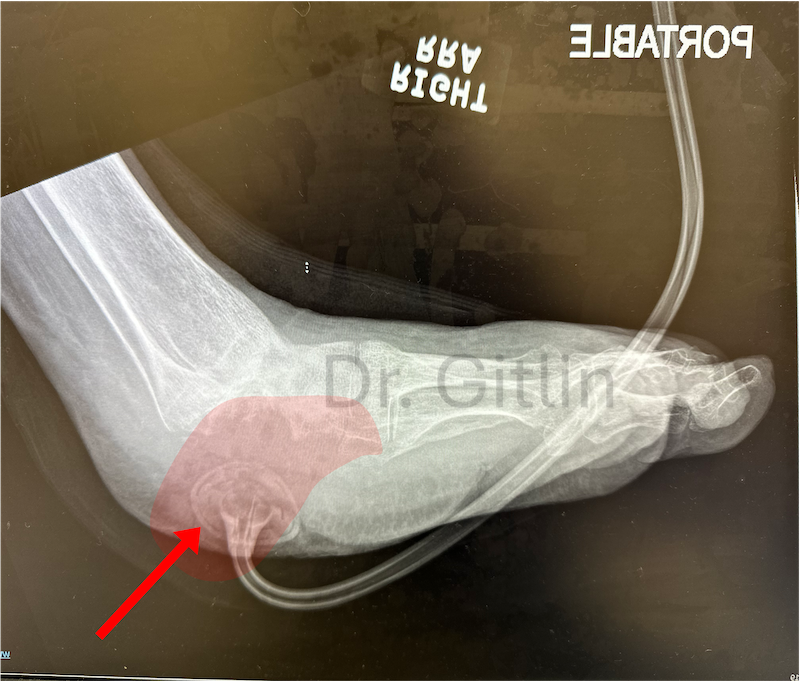

The X-ray below shows in red color the area that we needed to fill with bone. In order to achieve this we cut the leg bone called the tibia and pulled a piece of that bone downward to lengthen the bone and then we turned the bone with the external fixator to replace the heel.